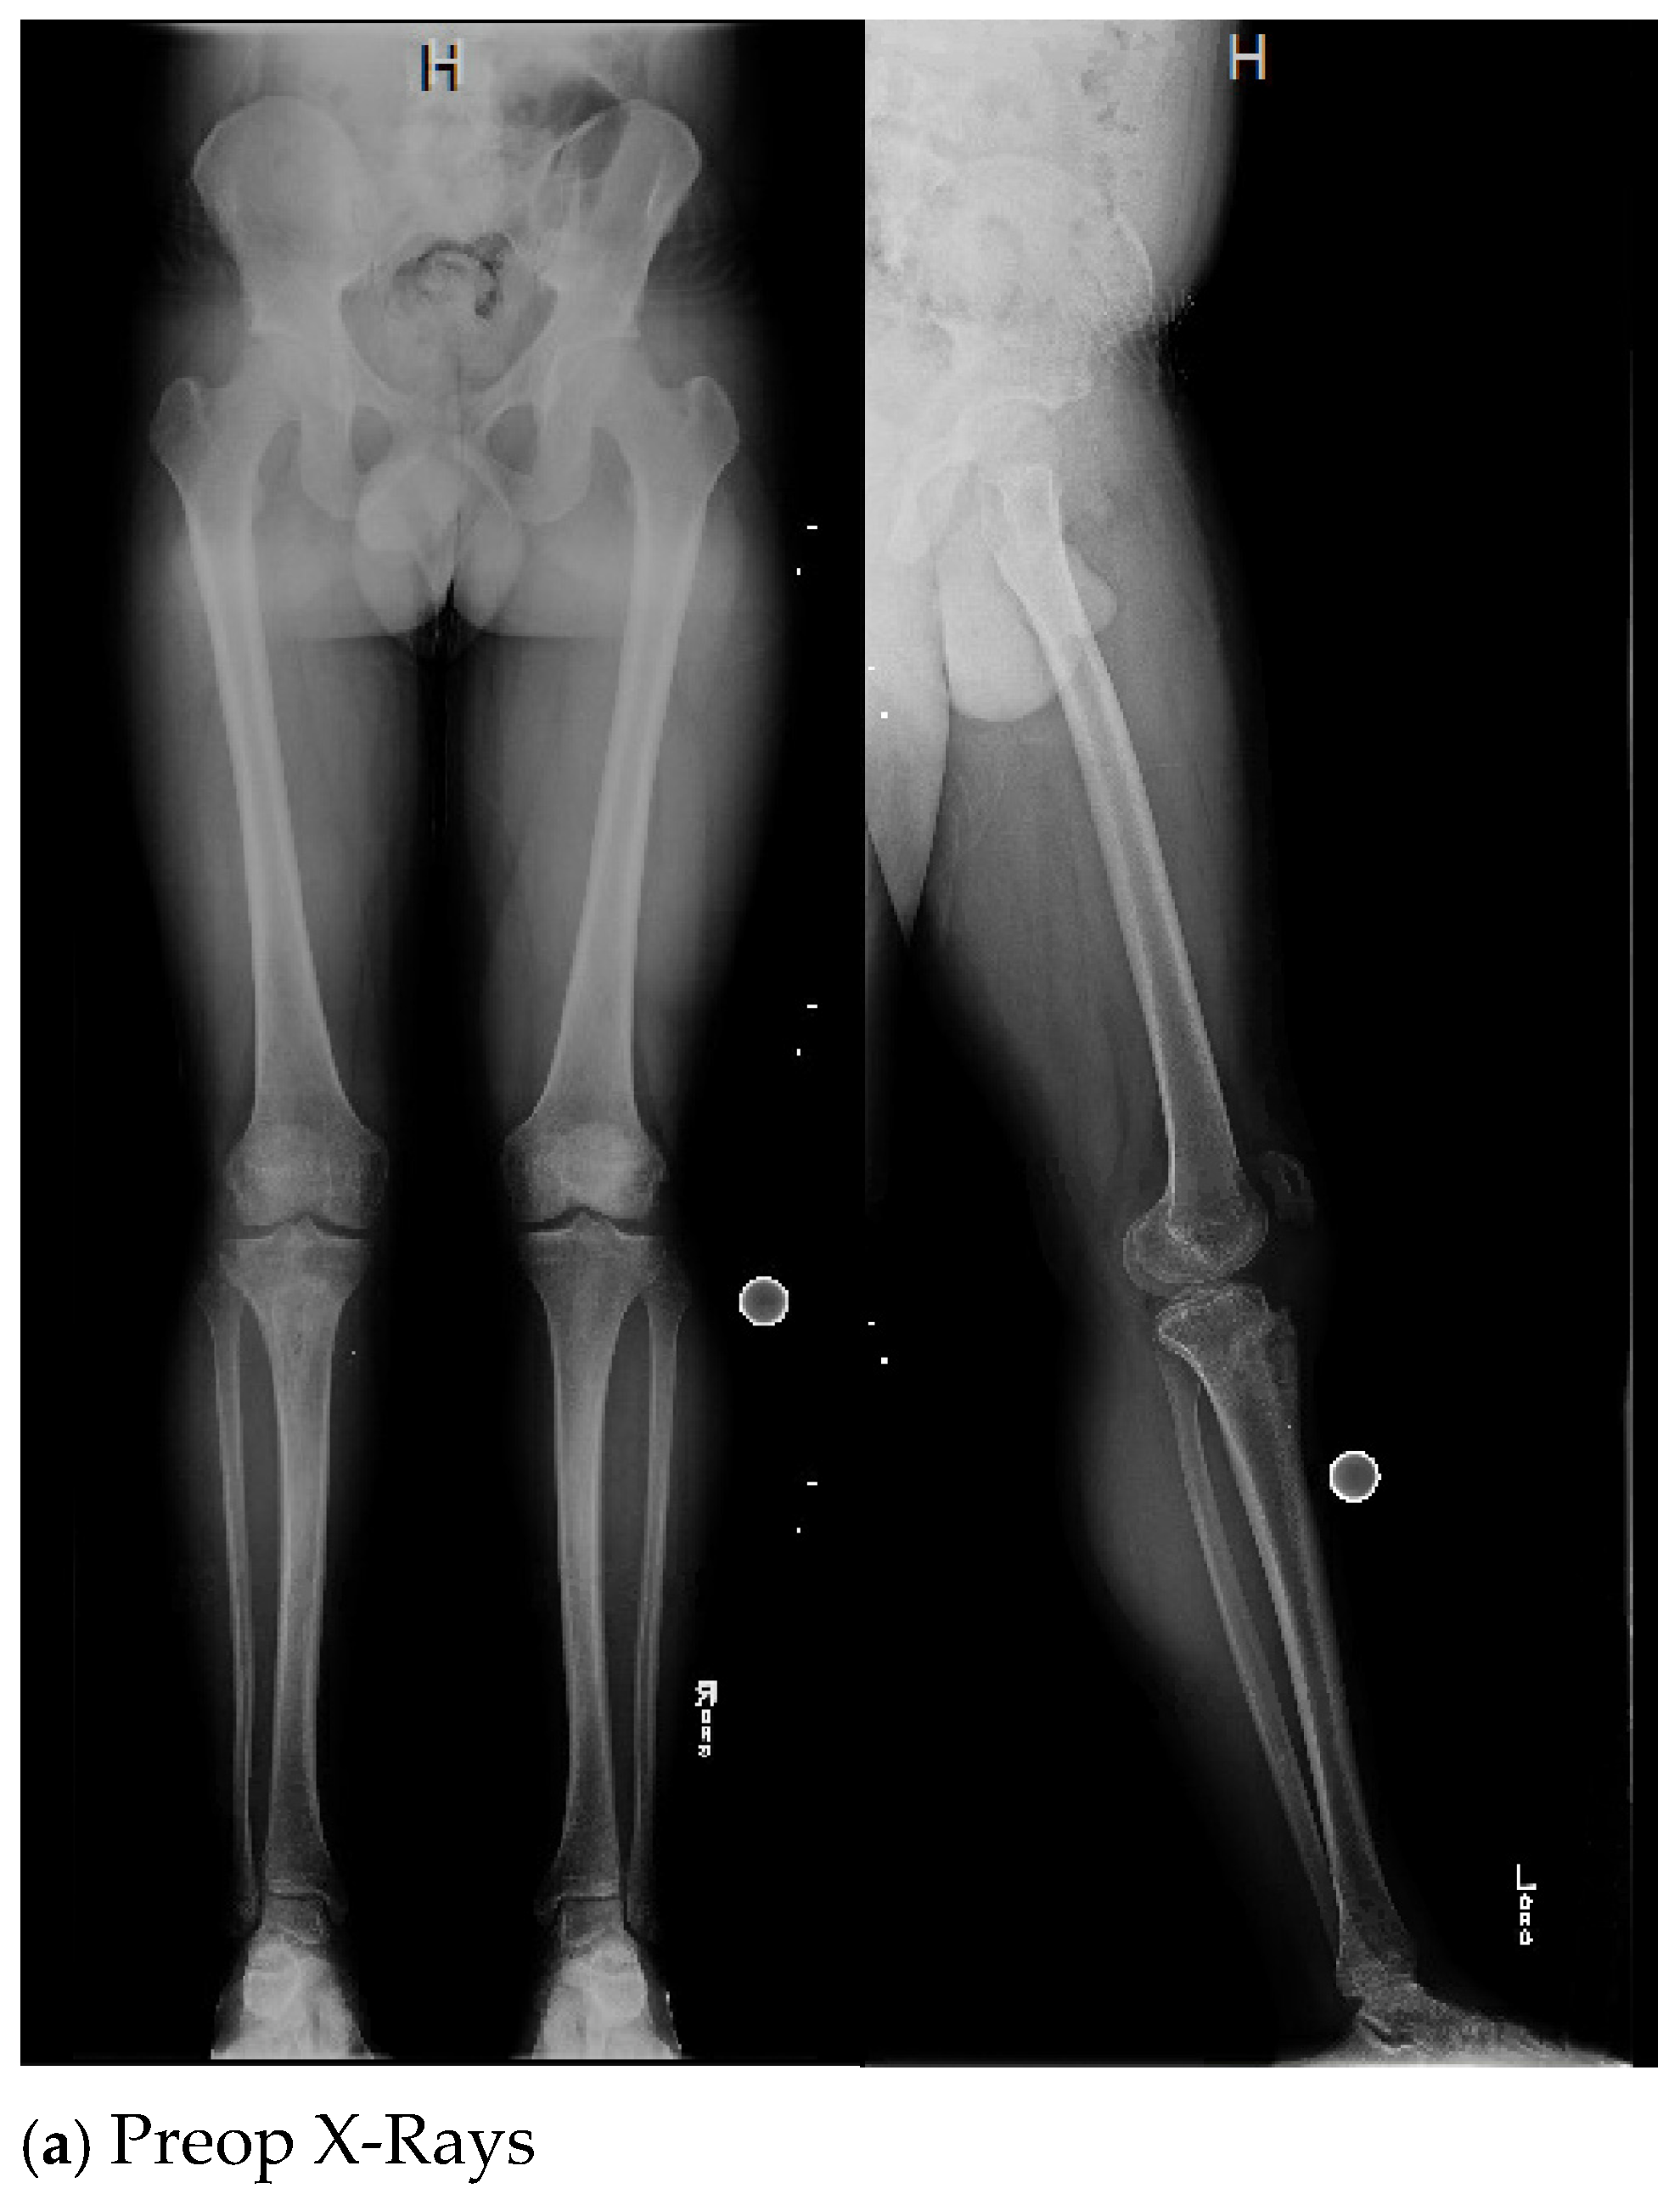

| 1. | 40 | F | N | N | 60 | N | N | 19 | Infected right distal tibia with bone defect and open wound |

| 1. | Y | Y (6) | 2 | 14 | Y, clinical and lab | 76 | 1st Op: Staphylococcus aureus 2nd Op: Serratia marcescens, Enterococcus faecalis |